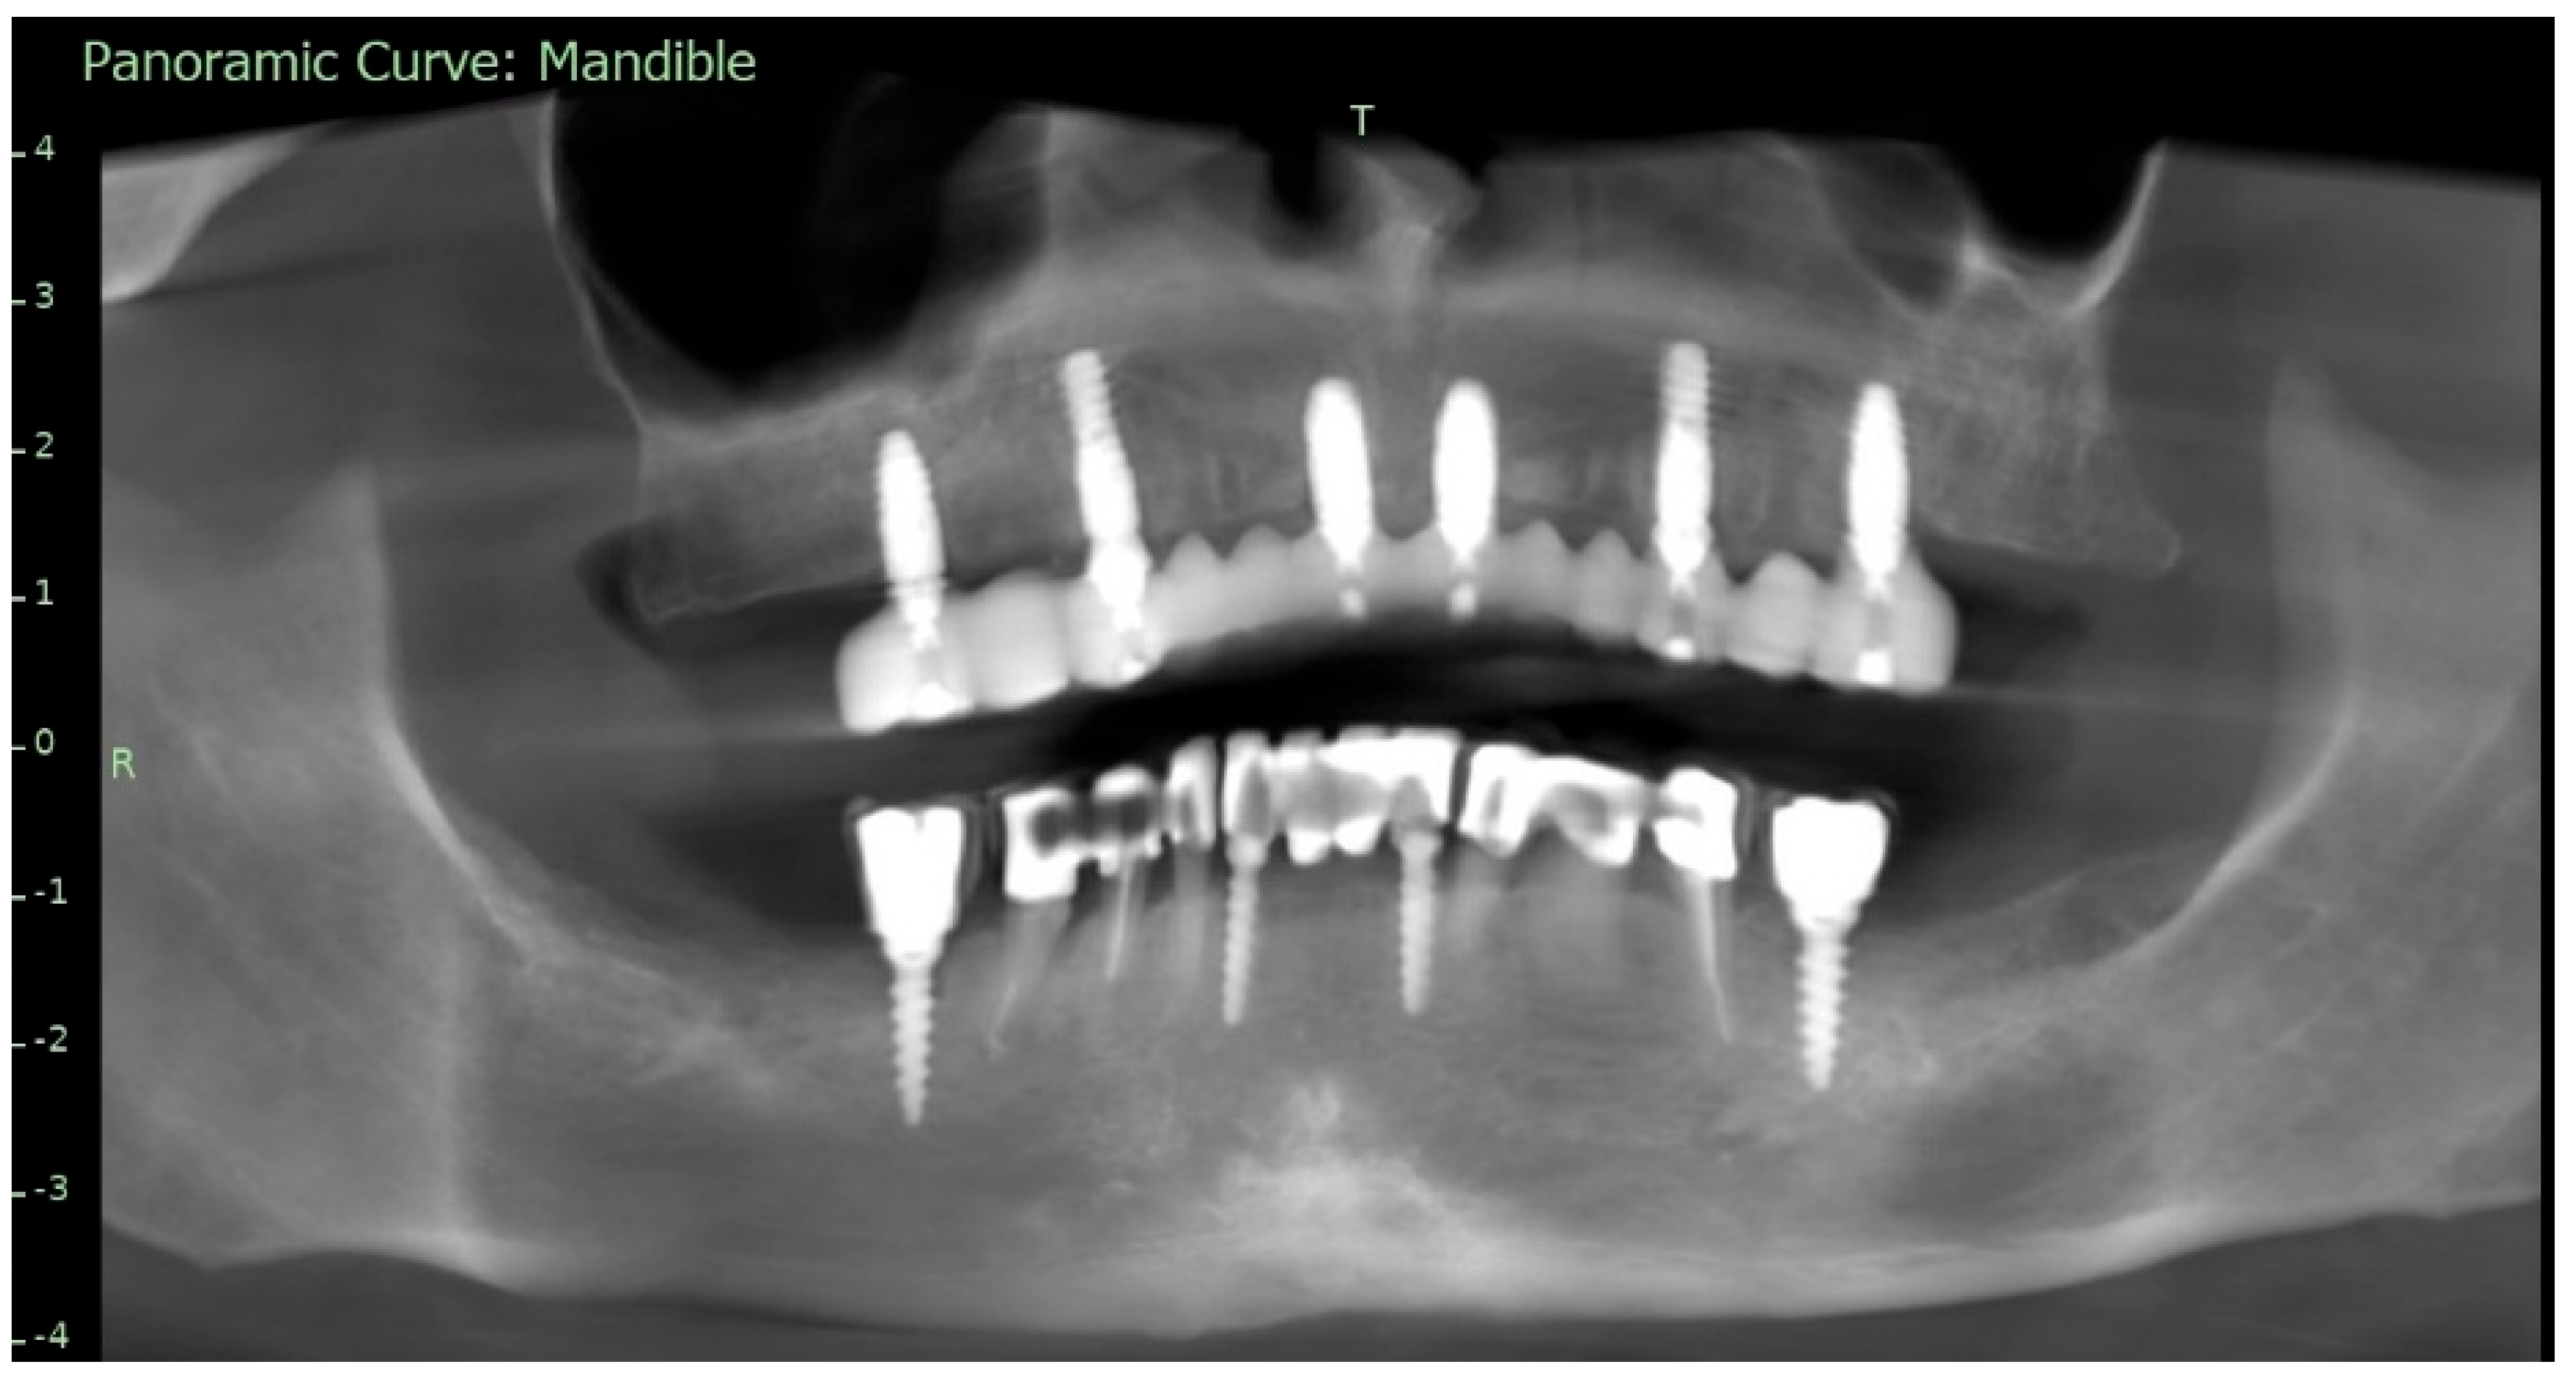

To supplement the clinical findings, a cone beam computed tomography (CBCT) scan was obtained (Figure 1) and evaluated. The implants existing in the maxilla demonstrated proper surrounding bone architecture. The compromised status of the remaining teeth was confirmed. In addition, the available bone conditions in the regions of teeth 14 and 24 were assessed to be adequate for future implant placement, particularly in the context of immediate implant insertion. This is in accordance with the literature emphasising that sufficient bone volume, labial plate integrity, and socket morphology, are critical prerequisites for successful immediate implant placement [7,8,9].

To verify the implant positions and the accuracy of the prosthetic fit, a control CBCT scan was obtained after the delivery of the early provisional restoration. Radiological evaluation confirmed stable positioning of the implants and correct seating of the prosthesis (Figure 11 and Figure 12).

Figure 1. Preoperative panoramic reconstruction from CBCT, showing the initial condition of the existing tooth- and implant-supported restorations in the maxilla and mandible, as well as the visualisation of two planned implants in positions 14 and 24.

Figure 11. Control CBCT scan obtained after the delivery of the early full-arch provisional restoration.

Figure 12. Control CBCT scan obtained after the delivery of the early full-arch provisional restoration.